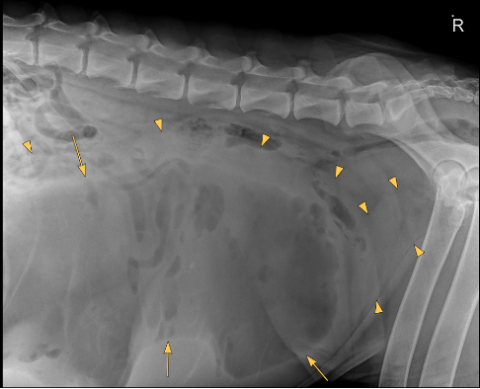

There is severe distention of the abdomen. As far as included the extra-abdominal soft tissues are within normal limits. There are 8 lumbar vertebrae, otherwise the bony structures are within normal limits.

A large well-defined, rounded soft tissue mass is noted in the caudal mid and cranial abdomen. The mass is filled with combination of fluid ( yellow arrow points) and gas (yellow arrows) and originating from the uterus.

The mass is displacing the gastrointestinal tract dorsally, cranially and laterally.

Large fluid and gas-filled mass in the caudal, mid and cranial abdomen originating from the uterus (emphysematous pyometra). Considering the shape of the mass a torsion is suspected.